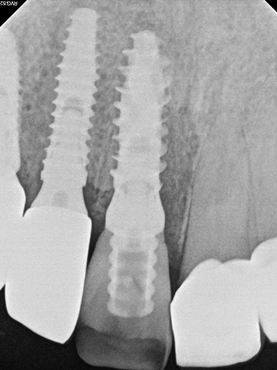

Post-operative radiographic image

Final radiographic image confirmed proper seating and integration.